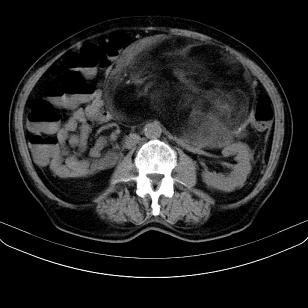

标题: CT21671:男,88岁,左上腹包块 [打印本页]

标题: CT21671:男,88岁,左上腹包块

患者因咳嗽而住院,自觉右上腹包块,无其他不适。

腹膜后高分化脂肪肉瘤

腹膜后脂肪肉瘤

腹膜生占位性病变,脂肪肉瘤可能。

左侧腹膜后脂肪肉瘤。